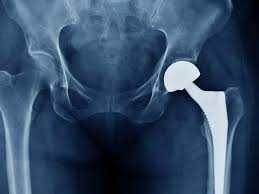

Precision hip replacement in Adilabad involves replacing the damaged components of the hip joint using meticulously planned surgical techniques. Moreover, this method prioritizes accurate implant positioning based on individual bone structure and joint orientation. As a result, the reconstructed joint is designed to closely replicate natural hip movement, which is essential for maintaining balance, posture, and overall musculoskeletal harmony in daily life.

Precision-based techniques enhance surgical accuracy by incorporating advanced imaging, digital planning, and alignment-focused instrumentation. Consequently, surgeons are able to visualize joint anatomy in greater detail before entering the operating environment. Moreover, this level of preparation allows for controlled execution during surgery, ensuring that implant placement supports optimal joint mechanics and minimizes alignment-related complications.

Advanced medical technology plays a vital role in enhancing the reliability of modern hip replacement procedures. Therefore, tools such as high-resolution imaging and precision-guided surgical systems assist surgeons in maintaining consistency throughout the operation. In addition, technology-supported workflows reduce procedural variability, which is critical in achieving predictable and medically sound outcomes for complex joint reconstructions.